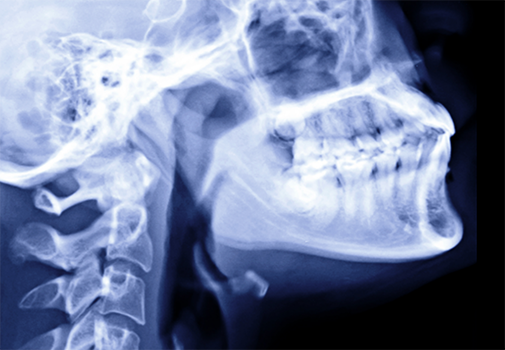

The biggest factor that makes a patient a good candidate for All-On-X (also called “Teeth-in-a-Day”) is the quantity of and strength of the jawbone that will hold the implants. In short, if the bone is dense enough to provide a stable foundation for the new teeth, then you would be a good candidate! One of the biggest advantages of All-On-X is that now with remote anchorage (zygomatic, transnasal, or pterygoid implants), compared to traditional dental implants, less quantity and/or quality of bone is required, so this approach enables nearly every patient to get implants who previously wasn’t a good candidate for them.